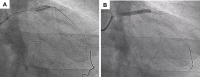

Abbildung 1A-B: Single NC-ballon applies very high pressures uniformly against the diseased arteries’ wall (A). Buddy balloon technique using 2 NC-balloons delivers the same pressures but causes tensile forces facilitating plaque fracture in severely calcified lesion (B).